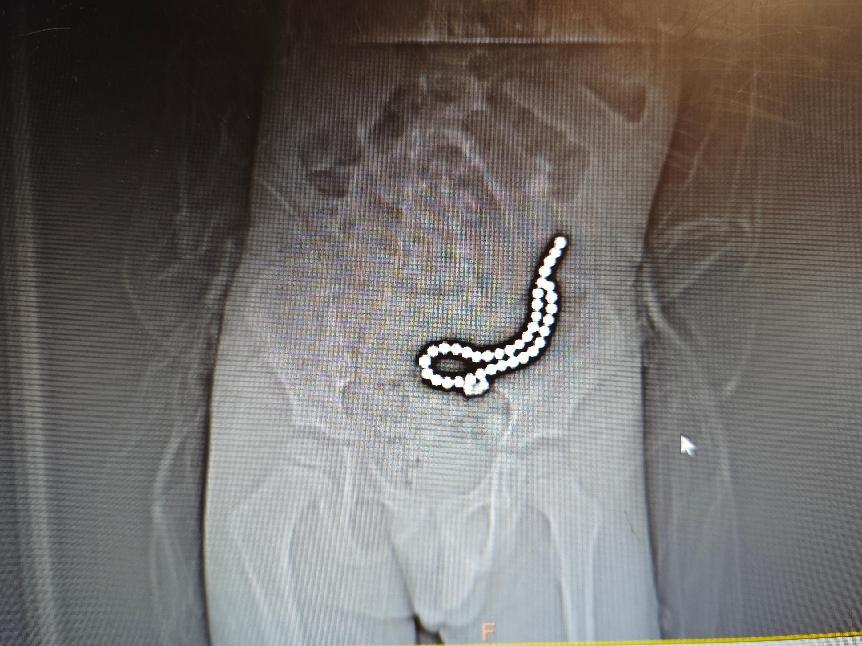

整整37颗

丽江4岁孩子身体里取出一串磁力珠

近日,丽江市人民医院接收了一名4岁患者。据了解,孩子在家中玩耍时不慎吞下了多达37颗磁力珠。医院紧急手术,成功取出了孩子体内的异物。【点击查看详情】